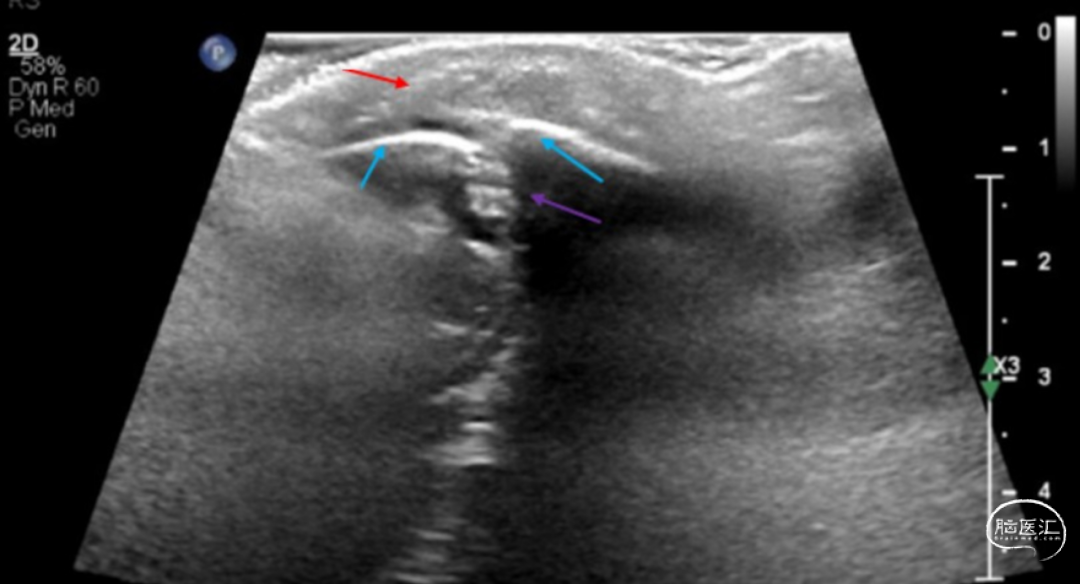

■ 脑部MRI显示后颅窝占位性病变(2.6×3×2.7cm),压迫小脑蚓部,伴幕上脑室扩大(图2)。因病变体积大、有占位效应,伴梗阻性脑积水及神经功能恶化,决定再次手术。

图2. 随访MRI检查显示小脑中线病变,伴继发性幕上脑室扩大,病变后部致密部分存在弥散受限,符合皮样囊肿表现。